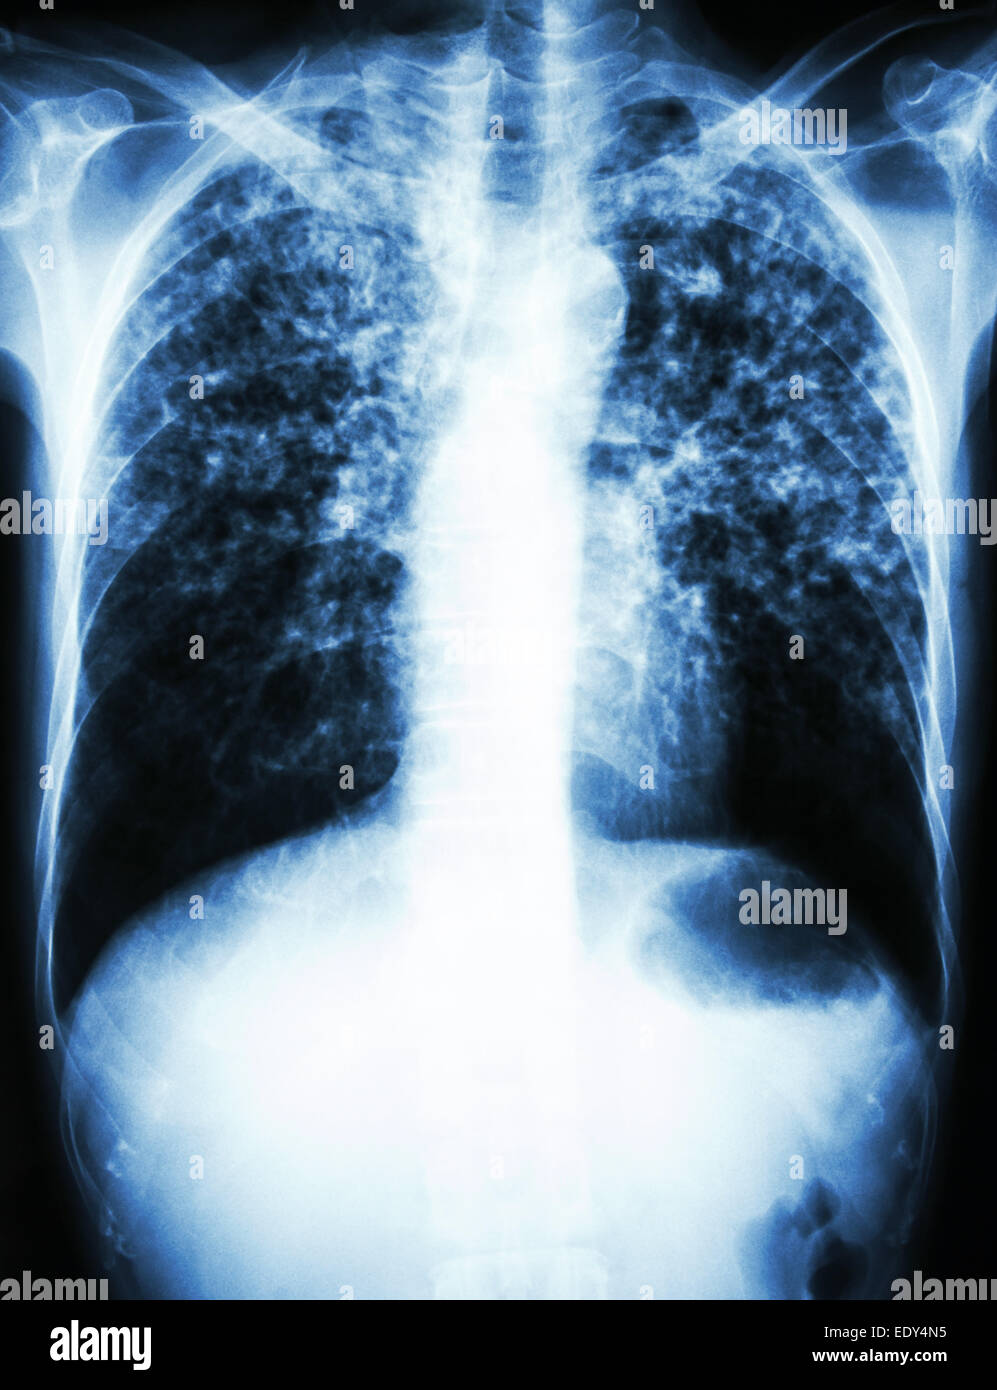

From www.alamy.com

Pulmonary Tuberculosis . Film chest xray show interstitial infiltrate both lung due to Do Chest X Rays Show Tb The only sign that you have a tb infection is a positive tb skin test or blood test. Prompt diagnosis of active tb. More tests, such as a chest radiograph, are needed to rule out tb disease. A positive result from a tb blood test or tb skin test usually means tb infection. In 2022, approximately 7.5 million individuals became. Do Chest X Rays Show Tb.